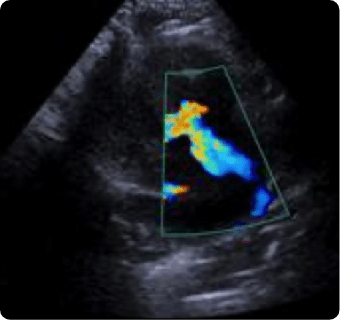

일산시티동물의료센터는 지멘스에서 개발한 고성능 프리미엄 초음파 장비인

Siemens Sequoia를 활용하여 심장, 복부 장기, 림프절 등의 구조물을 선명하게 구현하고,

미세한 해부학적 구조까지 정밀하게 확인할 수 있습니다.

이 장비는 대표적인 심장 질환인 이첨판 폐쇄부전증과 비대성 심근병증,

그리고 선천성 심혈관 질환인 동맥관 개존증, 심방중격결손, 심실중격결손 등을

진단하는 데 사용됩니다.

또한 급성 췌장염, 급성 신부전, 자궁축농증, 방광염, 요로결석, 소화기 이물,

비장종양 등의 질환을 진단하고, 환자의 상태를 평가하는 데에도 활용됩니다.